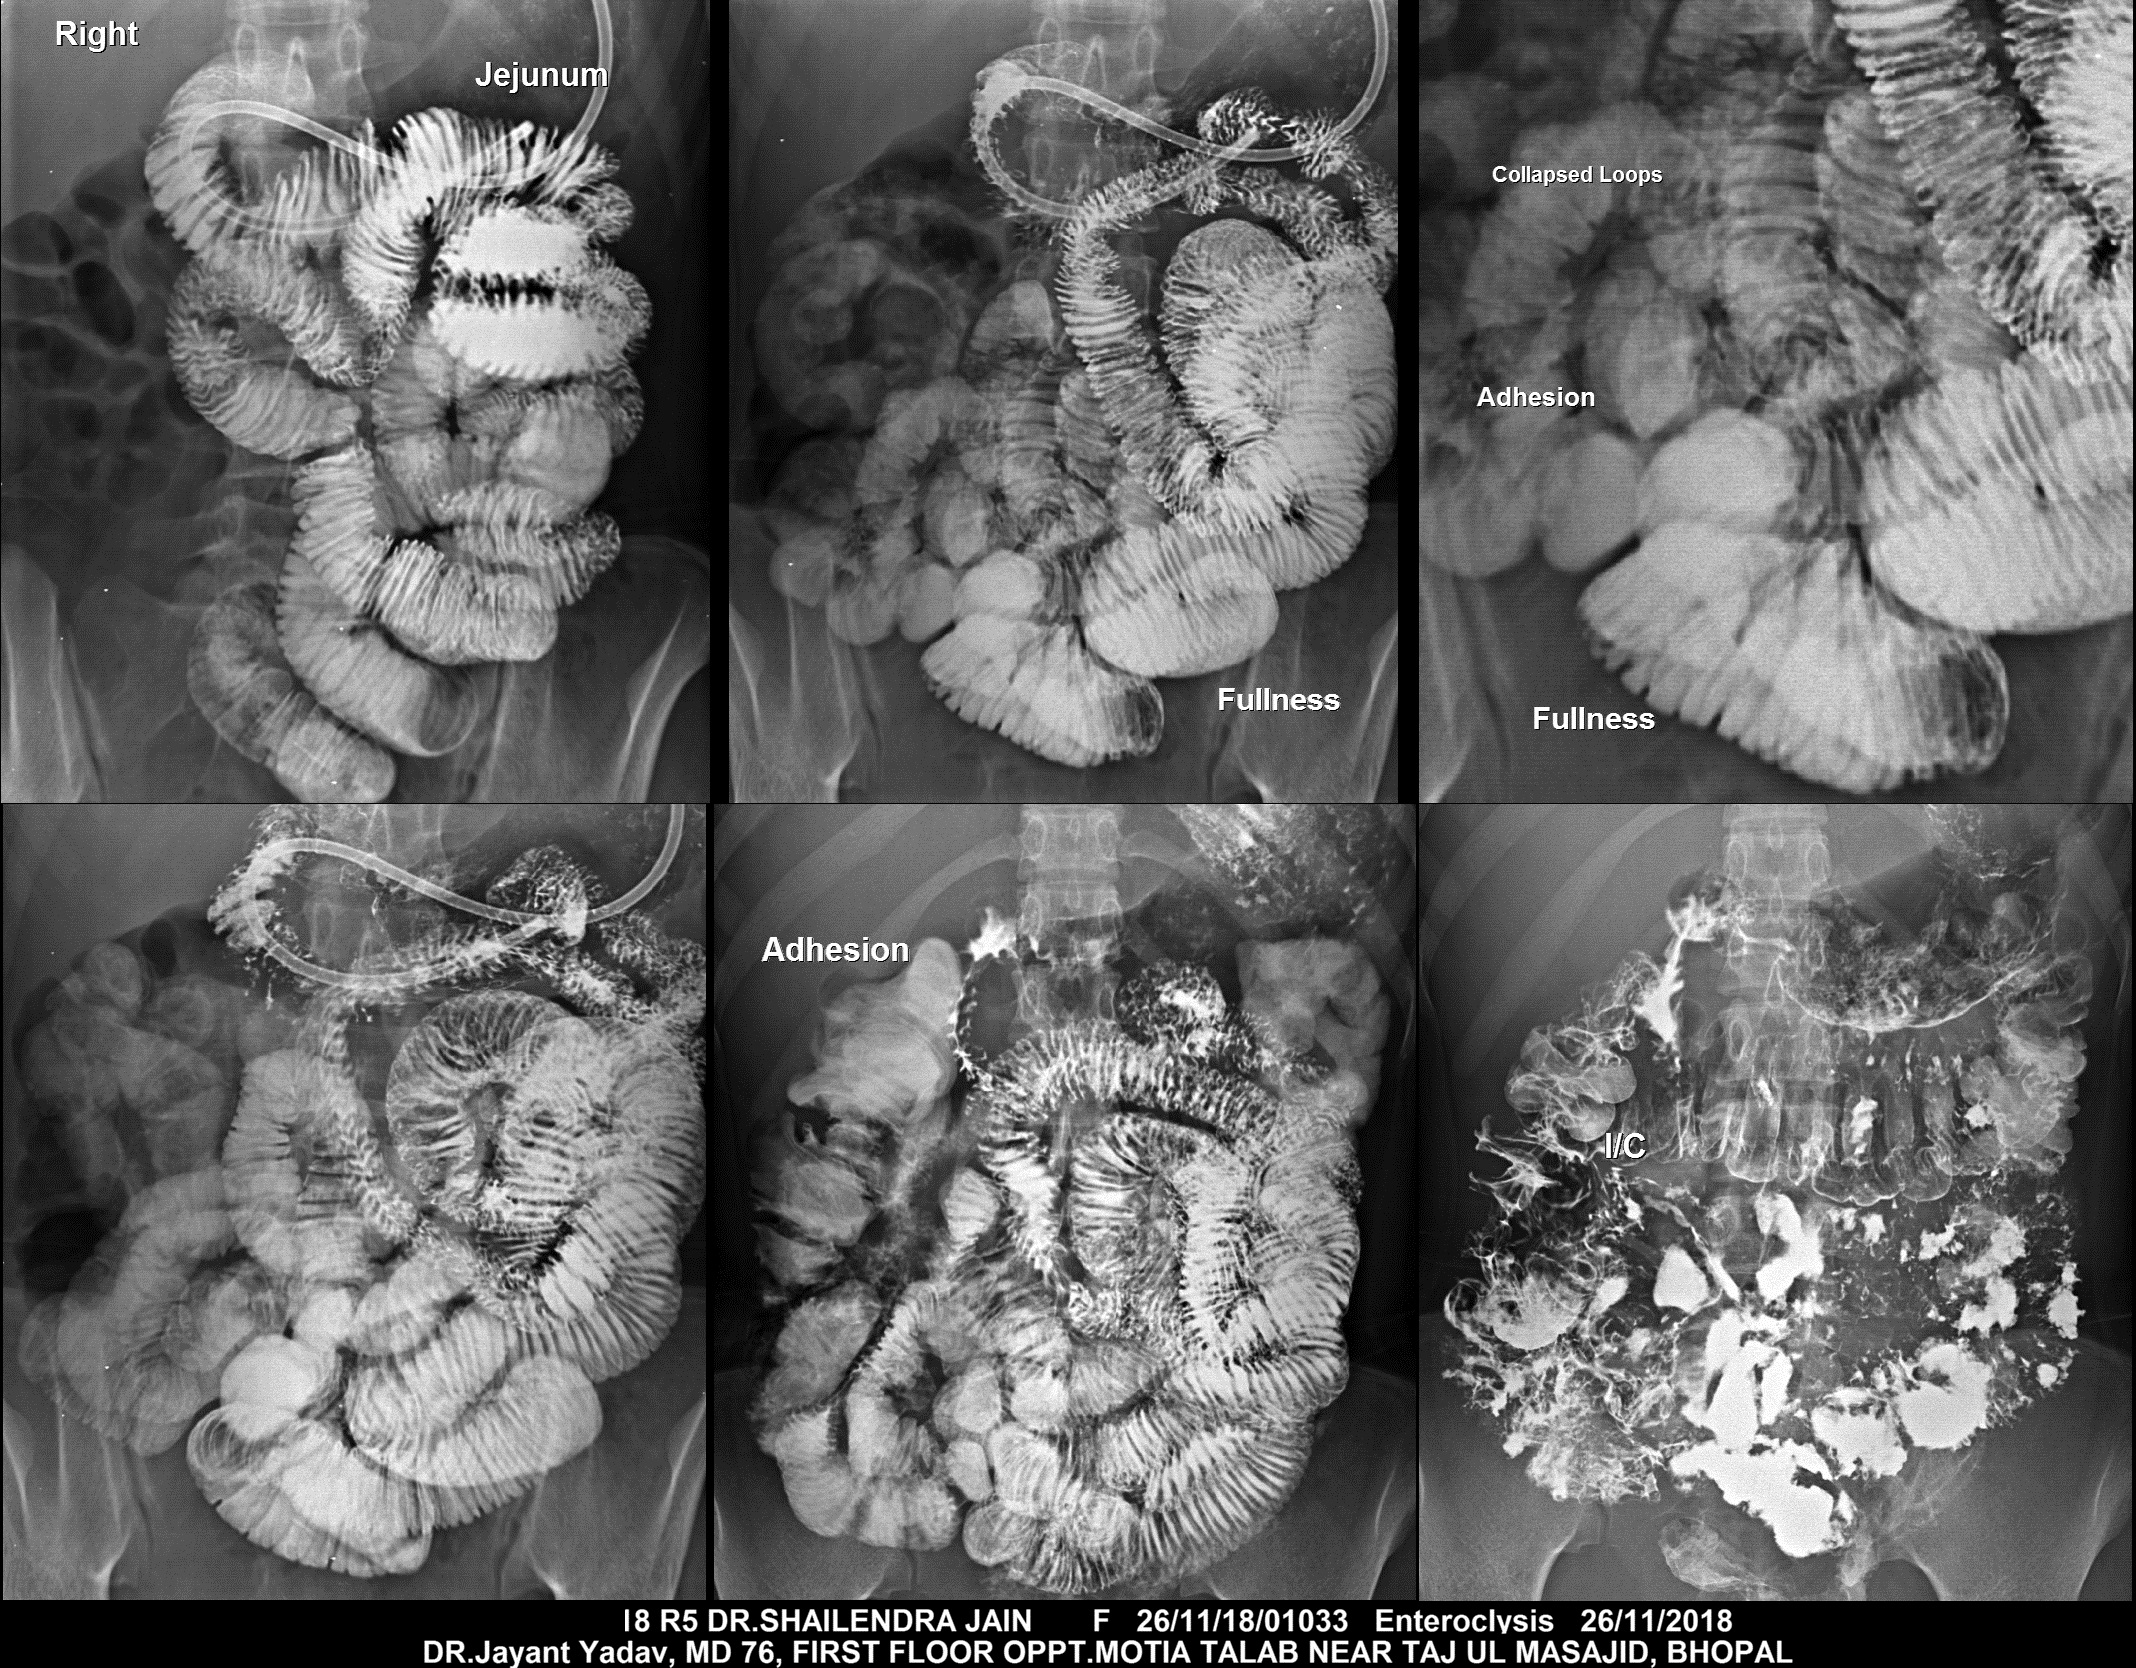

Section: ENTEROCLYSIS Total: 205 images

BaM Enteroclysis Loopogram BaE Fistulogram Urethrogram HSG